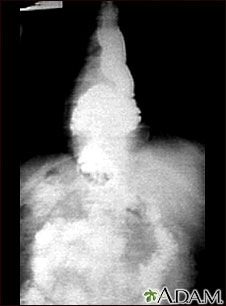

This x-ray shows the upper portion of the stomach protruding through the diaphragm (hiatal hernia).